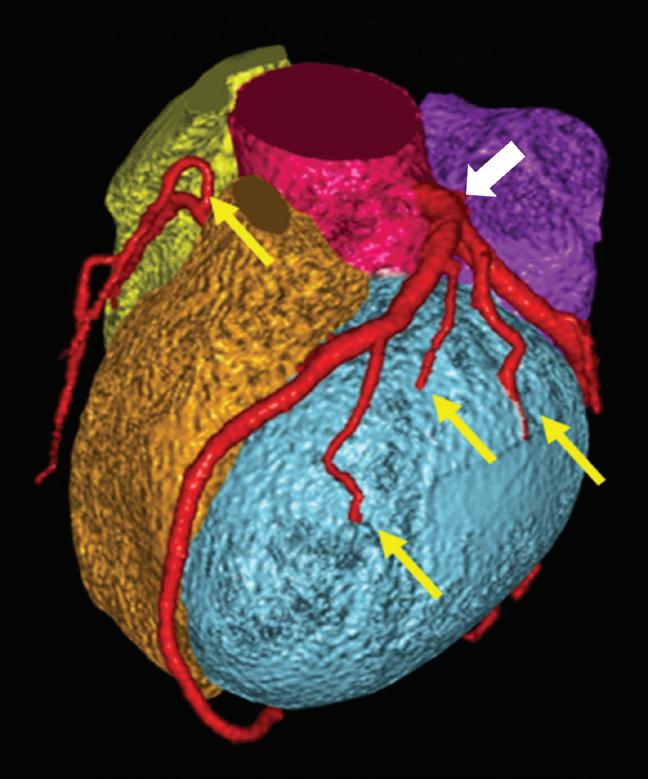

As Alvarez and Macovski wrote, the optimal material base must be selected phenomenologically taking into account the energy range and the materials the X-ray beam is expected to transverse. If bone and water are chosen as the base materials for the decomposition, the information from the low and high attenuation data can be used to calculate the bone coefficients of the X-ray attenuation. These coefficients can then be used to create a bone image which allows the assessment of bony structures and calcifications. Alternatively, the water coefficients can be calculated to generate a soft tissue image where the bony structures are suppressed and which improves the visualization of structures previously hidden by bony anatomy. Any material pairs can be created from any other pairs as a linear transformation post-decomposition: a change of base. Other pairs of base materials with clinical relevance are iodine and calcium, iodine and water, or calcium and water. In cardiovascular imaging, the iodine images from an iodine-calcium pair can be of primary importance because they can help to better assess the iodinated lumen of the arteries which could be otherwise hidden by the presence of large calcified plaques. The water images from an iodine-water pair are ones in which all of the iodine is removed. These virtual non-contrast images (VNC) synthesize a pre-contrast scan.11,12 The water images from a calcium-water pair are ones in which all of the calcium is removed. These calcium suppressed images (CaSupp) can be used to improve the visualization of the bone marrow edema which is partially hidden by the presence of the bony structures in the conventional CT images.13